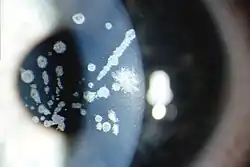

| Granular corneal dystrophy type I, Numerous irregular shaped discrete crumb-like corneal opacities | |

Granular corneal dystrophy is diagnosed during an eye examination by an ophthalmologist or optometrist. The lesions consist of central, fine, whitish granular lesions in the cornea. Visual acuity is slightly reduced.